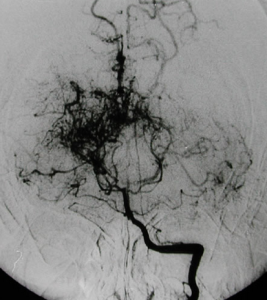

Moyamoya是日語"煙霧"的發音。本病的實質是腦底部動脈主幹閉塞伴代償性血管增生。本病的其他名稱有:煙霧綜合徵、煙霧病樣綜合徵、小兒WiIIis氏環閉塞症、小兒特發性進行性Willis氏環閉塞症等。治療方案